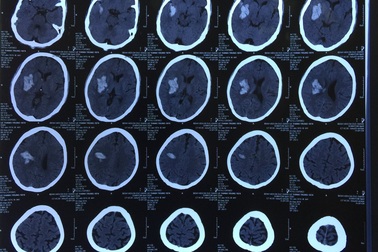

Phát hiện chảy máu não sau 1 tuần bỗng nhiên đau đầu, nói ngọngSau một tuần xuất hiện triệu chứng nói ngọng, đau đầu, bệnh nhân vào viện được các bác sĩ phát hiện có khối máu tụ trong não. Bệnh nhân nhanh chóng rơi vào tình trạng hôn mê, liệt nửa người. Ngay lập tức, bệnh nhân được phẫu thuật mở sọ cấp cứu, giải phóng chèn ép cho não.

Ghép sọ cứu bé trai 37 ngày tuổi bị chảy máu não vì thiếu vitamin KBé trai 37 tuổi được gia đình đưa đến BV Sản Nhi Quảng Ninh trong tình trạng quấy khóc từng cơn, li bì, bỏ bú kèm theo có nôn trớ sau ăn, da nhợt nhạt. Các bác sĩ phát hiện bệnh nhi yếu nửa người bên phải, đồng tử 2 bên không đều, thóp căng phồng, phản xạ yếu, thở rên… với chẩn đoán trẻ bị Tăng áp lực nội sọ/ xuất huyết não.